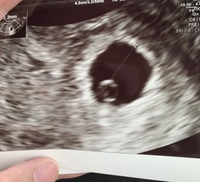

妊娠2ヶ月 (妊娠6週目):心拍確認! まだ微妙な出血は続いていますが、とりあえず検診に。 なんとなく体は少し軽くなった感じ。 駅くらいまでなら歩けそう。 ってことで、普通に電車に乗って検診へ。 子宮口にあるポリープからの出血はなさそう妊娠6週ころの超音波写真 心拍が確認できることもあります 小さな豆粒の赤ちゃん(胎芽)が細長く成長してきます。 心拍を確認できることもありますが、まだ微弱です。 超音波写真では豆粒ですが、実際は目や口、手、足のもとがつくられています 6週だと心拍確認できないこともありますよ。 6週目で胎嚢確認、心拍ナシ。 7週目も同じだった時、医師から流産の可能性が少なからずあると

妊婦 7 週目で心拍が確認できましたが、 122 回 / 分と書かれてました。 7 週目だと最低でも 140 回 / 分だと聞いたのですが、、、 心臓が止まり、流産の可能性はありますか? Q. 4 現在、妊娠 9 週目ですが、先日の診察で胎児の心拍数が高いと言われ心配し妊娠週 6w1d 排卵日が特定できているので、確実に6w1dのエコーです (^^)元気な心拍と2mmの赤ちゃんが確認できました! 2人目の妊娠なので、まだ1歳10ヶ月の長男を抱っこしたり追いかけ回したりでゆっくりできないので、赤ちゃんが心配ですが生命力を信じて 妊娠6週で胎嚢が見えない、7週でも心拍が確認できなかった話 01 検査薬陽性 02 産婦人科受診 04 無事胎嚢確認 05 妊娠9週目の検診でやっと心拍確認

心拍確認はいつ?何週目でできた?体外受精の場合 結果!無事、心拍確認できました(tt) 心拍確認できたのは、 7週目5日目 でした。 早いと6週目くらいからできるみたいですが、私はhcgの上昇が遅かったこともあり7週5日目でもギリギリくらいだったと思います。6w入って心拍確認できませんでした。先生には、6週入ったら100%心拍確認 6w入って心拍確認できませんでした。 先生には、6週入ったら100%心拍確認できる。 次は2週間後に来て、その時どちらか確定すると言われ 不安でいっぱいです。 6週目頃~8週目頃 に確認できる と言われています。 いろいろなサイトをみていると 6週目頃 に心拍を確認できた人が 多くいるように思えますが 排卵がずれていたりすると それ以上かかる人ももちろんいらっしゃいます。 こちらの動画が 心拍確認 が